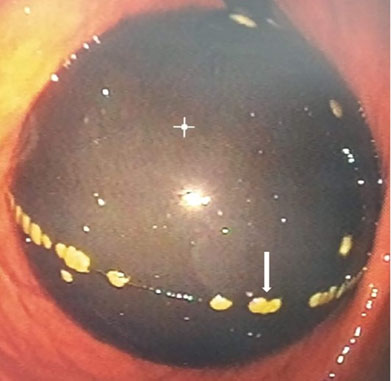

The chest X-ray showed mild cardiomegaly and a concave left middle arch. Computed tomography (CT) angiography image through the level of pulmonary trunk in the arterial phase showed the presence of low-dense occlusive intra-arterial material in the proximal pulmonary arteries bilaterally (Figure 1) and a reflux of contrast material into the inferior vena cava (IVC) and hepatic veins (Figure 2). For treatment, the patient benefitted from thrombolysis in emergency and was put on anticoagulants for up to six months with a good evolution under treatment.

Figure 1: Axial CT angiography image through the level of pulmonary trunk in the arterial phase shows a bilateral nonopacification and a low-dense occlusive intra-arterial material in the right and left pulmonary artery.

Chest CT angiography and ventilation perfusion scan has established itself as the gold standard in the diagnosis of PE. Several prospective studies have shown the safety of excluding PE on the basis of negative CT angiography, in patients with a low clinical probability but positive D-dimers, and in patients with a high clinical probability. The typical finding of PE on CT pulmonary angiography is filling defects within the pulmonary arterial system. When the artery is viewed in its axial plane, the central filling defect of a non-occlusive thrombus is surrounded by a thin rim of contrast, which is called Polo Mint sign, or an adjacent thin stream of contrast. The embolus makes an acute angle with the vessel. The affected vessel may also enlarge. Acute pulmonary thromboemboli on non-contrast chest CT may appear as intraluminal hyper densities. Indirect signs of the severity of PE on CT chest angiography include signs of right heart strain such as increased right ventricle (RV)/left ventricular (LV) ratio (>1 in axial plane, >0.9 in 4-chamber reconstruction), flattening and ventricular septum inversion, and reflux of contrast material into the IVC and hepatic veins. Dual-energy CT holds much promise for the diagnosis and prognosis of PE [13],[14].